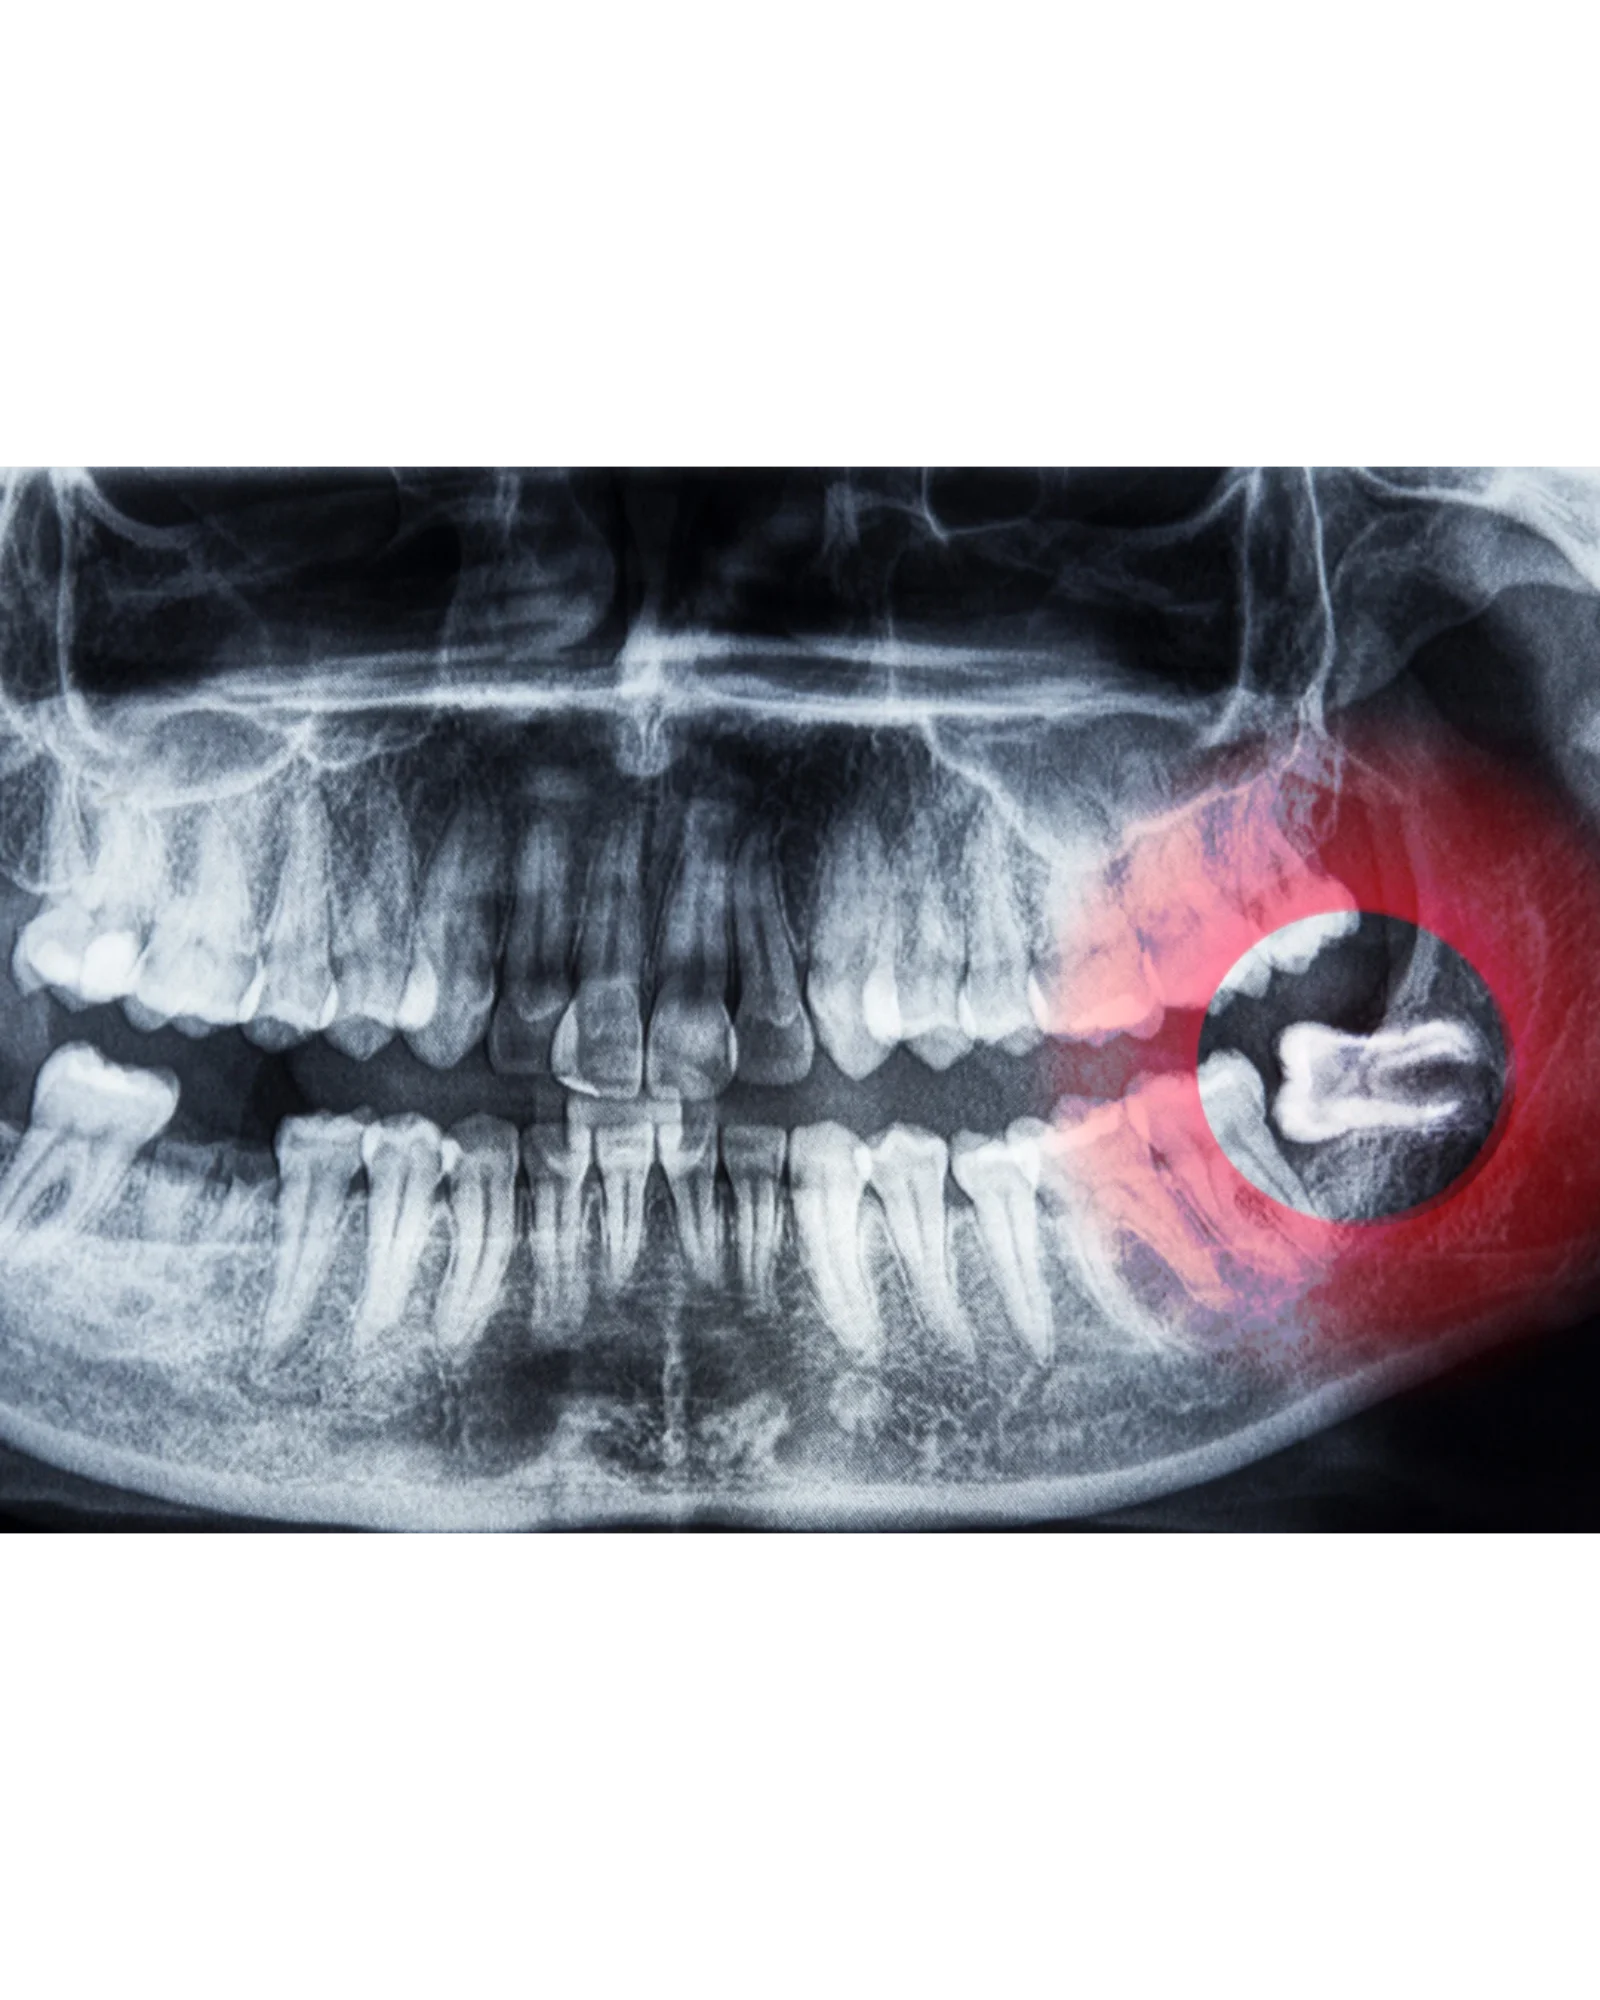

🦷 Ząb mądrości — kiedy lepiej się z nim pożegnać?

💡 Usunięcie tzw. „ósemek” to częsty i w wielu przypadkach konieczny zabieg, który pozwala uniknąć wielu powikłań w przyszłości.

➡️ Często rosną pod złym kątem, uciskając sąsiednie zęby.

➡️ Mogą powodować stłoczenia w łuku zębowym i bóle szczęki.

➡️ Trudno je dokładnie czyścić, przez co łatwo o próchnicę i stany zapalne.

➡️ Niekiedy zatrzymują się w kości, co prowadzi do torbieli lub infekcji.

✅ Dokładna diagnostyka z wykorzystaniem tomografii 3D, by ocenić położenie zęba i struktury anatomiczne.

📌 Wczesne usunięcie problematycznych zębów mądrości zapobiega przesuwaniu się zębów, stanom zapalnym oraz bólom głowy i stawu skroniowo-żuchwowego.